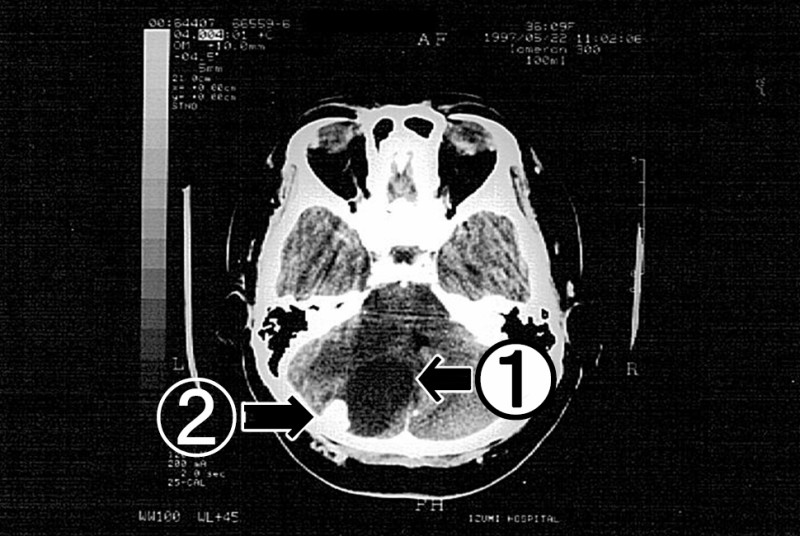

脳外科で施行したCTでは、左側小脳半球に直径5㎝程度の嚢胞を伴う腫瘍像を認め、第IV脳室の右方偏位が見られた(図2)。加えて眼底検査ではうっ血乳頭が確認され、水頭症の進行が懸念されたため、血管芽腫疑いとして即日入院となった。

図2 脳神経外科受診当日の単純CT。左側小脳半球に嚢胞①を伴う腫瘍②を認め、第Ⅳ脳室の右方偏移が見られた。

本症例は脳神経外科受診後、生命の危険を指摘され、即日入院となった。実際CT(図2)やMRI(図3・4)では、第Ⅳ脳室の圧迫と右方偏移・圧排された左側側脳室・大脳鎌ヘルニアなどの所見が得られ、眼底所見を併せて考えると水頭症の進行から脳幹の圧迫に至る危険性も、否定できなかった。